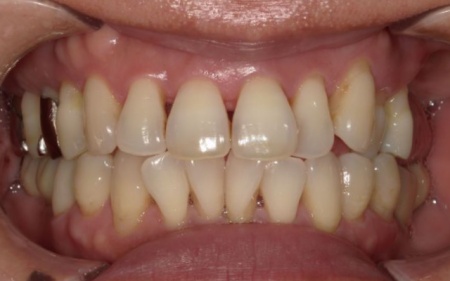

左上については、顎の骨が大きく失われているため、骨を再生させる処置「GBR(骨再生誘導法)」を実施してインプラントを支えるために必要な骨量を確保したうえで、インプラントを埋入する計画を立てました。

まずは左上奥歯2本を抜き、骨が足りない部分に骨補填剤を入れ骨の再生を促します。

経過観察後、十分な骨量を確保できたことを確認し、インプラントを埋入しました。

次に、右下に装着されているブリッジを除去してから右下の親知らずを抜き、欠損部(第1大臼歯、第2大臼歯の部分)にインプラントを埋入しました。

また、右下の手前にある奥歯2本(第1小臼歯、第2小臼歯)は、新しく詰め物を作製して噛み合わせと見た目を整えています。

続いて、インプラントに装着する人工歯を作製します。

最後に、完成した人工歯をインプラントに取り付け、噛み合わせや見た目に問題がないことを確認し、治療を終了しました。